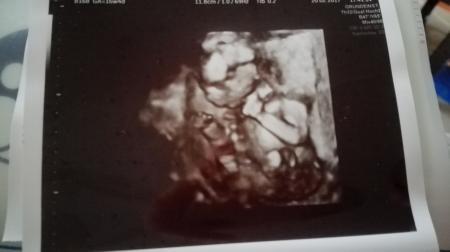

Haach Mädels seit gestern bin ich wie im Rausch Gestern Abend war wieder FA Termin. Zu erst hat die Schwester die Herztöne vom Bärchen gehört und da war ich ja schon hin und weg. Dann ging es rein zum Arzt. Wir waren so aufgeregt, mein Männe war extra mit. Ist der Zwerg gewachsen, ist alles dran und gesund und vorallem, erfahren wir was wir erwarten?! Zu erst war ich direkt erstaunt wie groß unser Bärchen schon ist und ein Stein fiel mir vom Herzen. Top fit und gesund Schon bevor der Arzt es aussprechen konnte, hab ich direkt erkannt als es zwischen die Beine ging, dass wir einen Sohn erwarten nach drei Mädels der erste leibliche Sohn für meinen Mann. Ach und ich sag's euch, seine Reaktion war so unglaublich rührend Und ja mein Wunsch ging damit auch in Erfüllung. Unsere Tochter bleibt das einzige Mädchen Hach ich kann garnicht aufhören mir die US Bilder anzugucken

Bild zu Unglaubliche Freude < 3 - Forum für August - Mamis

Bärchen ist von Kopf bis Po jetzt 11cm lang